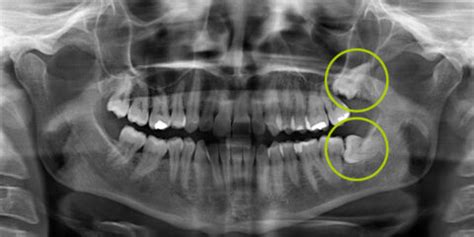

Los molares impactados pueden crecer en forma horizontal o en distintos ángulos respecto a la mandíbula. En ocasiones permanecen retenidos, lo que puede provocar daños en las raíces de las piezas adyacentes. También puede ocurrir que salgan solo de forma parcial, lo que favorece la acumulación de alimentos y bacterias.

Asimismo, pueden apiñarse contra el resto de los dientes y provocar cambios en su alineación. De hecho, son capaces de alterar los resultados de trabajos de ortodoncia previos al mover los dientes. Hay quienes recomiendan extraerlas antes de que comiencen a generar problemas. Para evaluar la situación se hace una radiografía en la que se ve su posición y ahí se decide qué hacer.

Radiografía mostrando muelas del juicio impactadas.